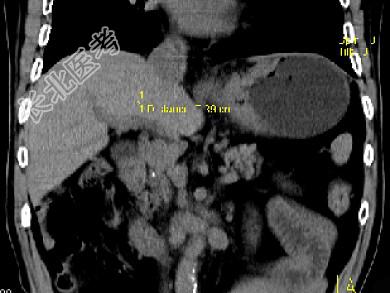

- 单项选择题男,75岁, 吞咽有梗阻感,消瘦、乏力、中上腹痛, 影像检查如图,最可能的诊断是 ( )

A、食管癌

B、胃窦癌

C、贲门癌

D、慢性胃炎

E、胃淋巴瘤